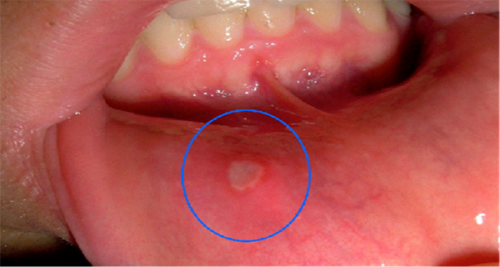

Trajtoni ulcerat e gojës me këto mënyra natyrale